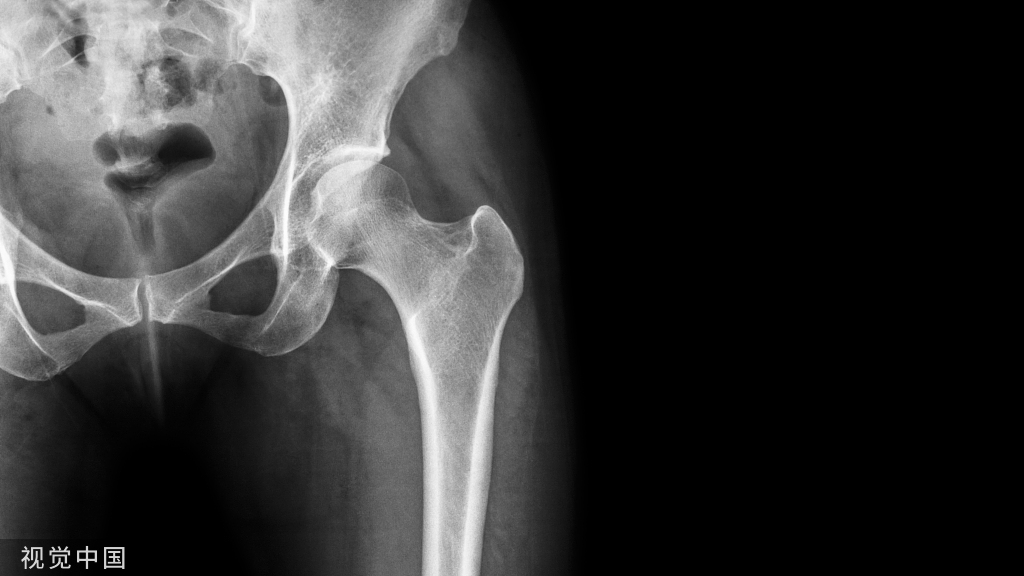

1、确定下肢关节的中心点(1)髋关节中心髋关节中心点由股骨头来确定,由于股骨头是相对比较规则的圆形,使用Mose圈或圆规就能确定股骨头中心也就是髋关节中心。

4、画出与机械轴相关的角度股骨近端外侧角(LPFA):沿股骨头中心与大粗隆最高点划一直线,连接股骨头中心与膝关节中心划一直线(机械轴),两者之间形成的外侧夹角,正常为90°±5°。

股骨远端外侧角(mLDFA):股骨内外侧髁远端切线(关节线)与股骨头和膝关节中心的连线(机械轴)两者之间形成的外侧夹角,正常为87°±3°。